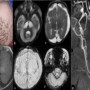

A 5month old male child born out of by non-consanguineous marriage presented with history of left focal seizure, reddish discoloration of left hand and delayed attainment of milestones. Parents also noticed increase in fairness of the baby and loss of hair.upper and lower limbs.

Figure : Image (a) The clinical images of the patient’s scalp shows fair complexion of the child with hypopigmented , sparse and short scalp hair (white arrows). The axial T2 (b & c) images shows bilateral subdural hygroma (asterix) with significant cerebral and cerebellar volume loss. The axial T1 image (d) shows delayed myelination , corresponding to birth. The axial susceptibility weighted images (e & f) shows extensive superficial siderosis along the cerebral sulcal and cerebellar folial spaces (black arrowheads). The time of flight MR angiogram image (g) shows tortuous intracranial and extracranial arteries (dashed arrows).

•Metabolic work up revealed low serum copper and ceruloplasmin levels.

FINAL DIAGNOSIS :Menkes disease (MD)

•Menkes disease (MD) is a rare lethal X-linked recessive disorder due to mutations in the ATP7A gene with incidence of 1 in 300 000 (1), causing impaired absorption and cellular metabolism of copper. Reduced activity of copper-dependent enzymes leads to abnormalities in connective tissue, blood vessels, and hair.

•MRI is the investigation of choice. Cerebral and cerebellar atrophy and delayed myelination are the earliest changes seen (2). Subdural collections are relatively common finding in all children with MDs (3). Basal ganglia can also be involved in Menkes disease, most vulnerable parts are the head of the caudate nucleus and anterior putamen followed by the globus pallidus and it is due to occlusion of small perforating arteries (4).Tumefactive lesions can also be seen, predominantly in temporal lobes which can be symmetric/asymmetric (4). Tortuosity of intracranial vessel is a typical diagnostic feature of Menkes disease (3). Stenosis and ectasia of intracranial vessels are not reported.